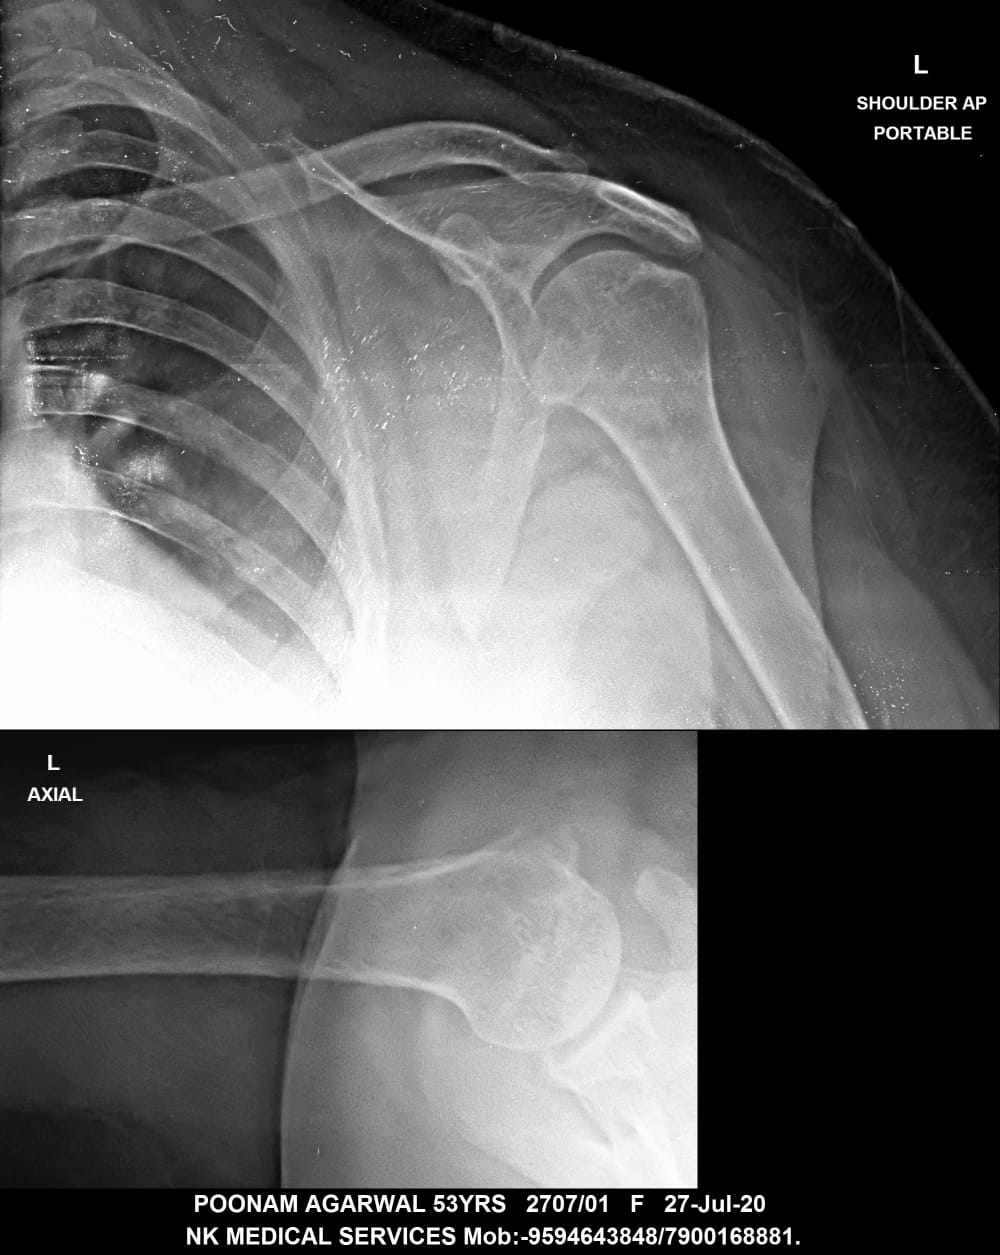

Getwell Urgent Care of Southaven uses digital X-ray technology, which uses less radiation, provides fast turnaround of images, and gives us the ability to manipulate images for more accurate readings. We follow the highest safety standards, with certified equipment and licensed radiology technologists to ensure an excellent image the first time and minimal exposure to radiation. We use digital X-ray to diagnose broken bones, certain lung conditions (e.g., pneumonia), and certain abdominal conditions.